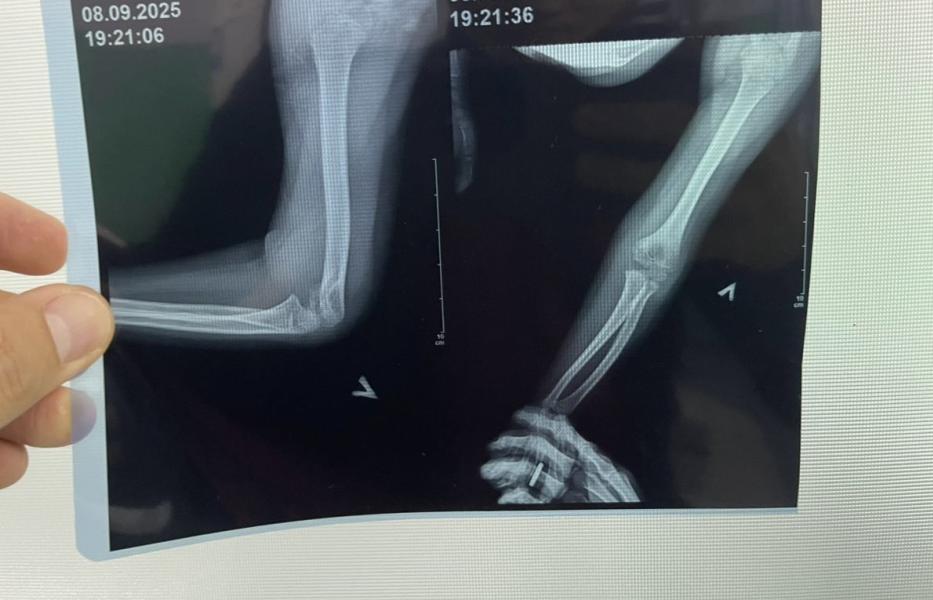

🆘 🆘 Мамочки, посоветуйте хорошего травматолога детского. У дочки перелом . Сегодня в 3 детской поставили гипс и врач сказал , чтобы завтра с утра пришли к заведующему, т к перелом в опасном месте и нужно будет проконсультироваться с заведующим.

Я хотела бы помимо заведующего еще к другому врачу съездить, показать дочку.